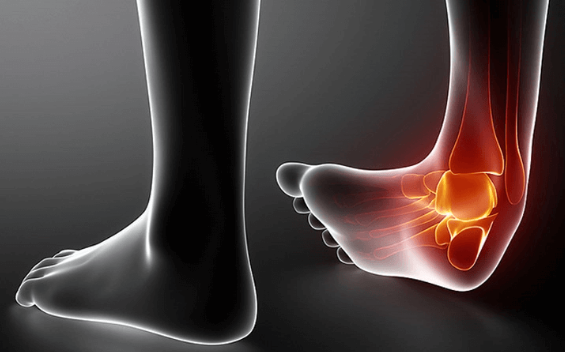

발목 통증?

발목 통증은 발목관절에 느껴지는 불편감이나 통증을 말합니다. 경증부터 중증까지 다양하며 갑자기 발생하거나 시간이 지남에 따라 점진적으로 발생할 수 있습니다. 발목 통증은 한쪽 또는 양쪽 발목에 영향을 미칠 수 있으며 다양한 요인에 의해 발생할 수 있습니다.